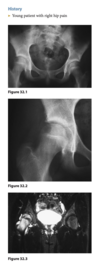

Sagittal proton-density (Fig. 2.14.1)

and fast spin-echo, T2-weighted fat-suppressed

(Fig. 2.14.2) MR images show an area of increased

signal intensity within the anterior cruciate ligament

(ACL), the so-called pseudo-mass (arrows); nonvisual-

ization of the normal ACL fibers; and a joint effusion.

A sagittal fast spin-echo, T2-weighted fat-suppressed

MR image through the lateral joint compartment

(Fig. 2.14.3) shows high-signal-intensity areas in the

subchondral regions of the midportion of the lateral femoral condyle and the posterolateral tibial plateau,

the so-called “kissing contusions”

Full thickness tear of the ACL

MRI features of the torn ACL include an irregular

or wavy contour with decreased angulation on the

sagittal images (i.e., “lying down” or vertically ori-

ented ACL), increased signal intensity on all MRI

sequences in the region of the ACL (i.e., so-called

“pseudo-mass”), posterior displacement of the lateral

meniscus (i.e., “uncovered lateral meniscus” sign),

loss of the normal obtuse curvature with increased

angulation of the posterior cruciate ligament, undu-

lation of the patellar tendon, and the “empty notch”

sign, which is also seen on arthroscopy.

Bone

impaction from transient subluxation results in

the characteristic osseous contusions involving the posterolateral tibial plateau and midportion of the

lateral femoral condyle (i.e., “kissing contusions”).